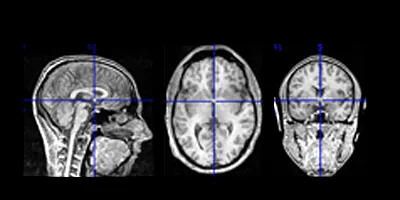

Structural magnetic resonance imaging (MRI) is a non-invasive technique for examining the anatomy and pathology of the brain (as opposed to using functional magnetic resonance imaging [fMRI] to examine brain activity. This produces images which can be used for clinical radiological reporting as well as for detailed analysis. Overview Purpose Detail Contact Professor Joanna Wardlaw Relevant links What is a MR scan? Brain & nervous system Some MRI scan sequences are volumetric, meaning that measurements can be made of specific brain structures to calculate volumes of tissue. These scans can also be reconstructed in any plane. The volumes of regional grey and white-matter (of which the brain is composed) change considerably during childhood and adolescence, and may change again in old age. There is considerable evidence as well that many psychiatric conditions are associated with abnormal (either increased or decreased) regional brain volumes compared with age- and sex-matched healthy subjects. These volumetric scans are also used to map fMRI and DTI scans which have low resolution with associated structures. Many projects depend on detailed structural imaging to measure brain volumes, the volume of subregions, to look at diffuse changes in grey/white matter or to assess localised lesions. Such studies include comparing the appearance of a cerebral infarct on different imaging modalities over time and relating these to the patient's clinical features and outcome. They may also determine whether those from families at risk of developing psychiatric disorders have subtle but significant differences in brain structure in particular regions of the brain which are thought to malfunction at the time of the development of symptoms. Many of these studies simply involve having a highly trained neuroradiologist read the images, but others require detailed image analysis with computers and software packages that can be very time consuming and labour intensive, even with modern machines. Careful discussion is always required prior to the start of a project to determine the amount of analysis that might be required. Image The above figure shows structural images measuring tissue density. Staff contact If you wish further information on the above activities, please contact Prof Joanna Wardlaw. Prof Joanna Wardlaw This article was published on 2024-08-22